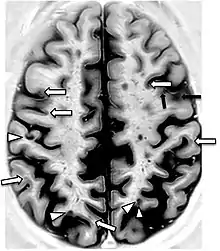

A 2019 literature review identified hypertension and a history of preeclampsia as significant risk factors for the accelerated decline of cognitive function in women during midlife. Although the mechanism remains unclear, neuroimaging studies included in the review have revealed that those with hypertension have evident structural changes in their brains. Specifically, gray matter brain volume decreased and white matter hyperintensity volume increased.[19]